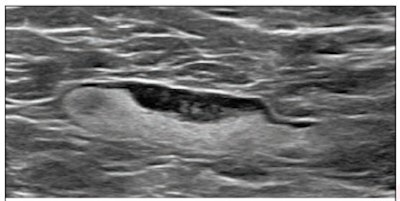

(Above) 55-year-old woman who underwent screening mammogram and ultrasound seven days after first COVID-19 vaccination dose. Screening mammogram and US demonstrated unilateral left axillary lymph node with cortical thickness of 5 mm on ultrasound (not shown). BI-RADS category 0 was assigned. Ultrasound from diagnostic work-up performed seven days later showed no change in lymph node size. BI-RADS 3 was assigned. (Below) 41-year-old woman who underwent high-risk screening breast MRI 15 days after first COVID-19 vaccination dose. Sagittal T1-weighted fat-saturated contrast-enhanced MRI shows extensive unilateral left level I-II axillary adenopathy. BI-RADS 3 was assigned. Images and captions courtesy of the American Roentgen Ray Society.

(Above) 55-year-old woman who underwent screening mammogram and ultrasound seven days after first COVID-19 vaccination dose. Screening mammogram and US demonstrated unilateral left axillary lymph node with cortical thickness of 5 mm on ultrasound (not shown). BI-RADS category 0 was assigned. Ultrasound from diagnostic work-up performed seven days later showed no change in lymph node size. BI-RADS 3 was assigned. (Below) 41-year-old woman who underwent high-risk screening breast MRI 15 days after first COVID-19 vaccination dose. Sagittal T1-weighted fat-saturated contrast-enhanced MRI shows extensive unilateral left level I-II axillary adenopathy. BI-RADS 3 was assigned. Images and captions courtesy of the American Roentgen Ray Society.